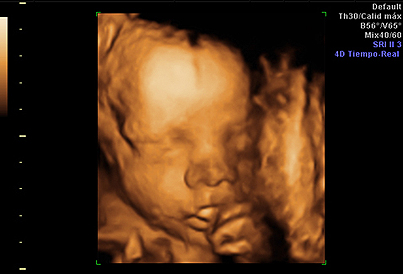

Todas las familias están deseando conocer la carita de su futuro bebé, y hoy en día muchas madres recurren a las ecografías en 4D, que ofrecen imágenes realmente impresionantes. A quién no se le ha caído la baba ante esas pantallas que nos muestran al feto como si ya estuviera fuera… Pero, ¿sabemos en qué consiste esta prueba? Y, si realmente solo existen tres dimensiones, ¿por qué se le llama 4D? A estas preguntas y otras nos contesta Inés Tamarit Degenhardt, especialista en Ginecología y Obstetricia.

Porque a las tres espaciales unimos el tiempo. Es decir, la ecografía 4D consiste en ver imágenes en 3D junto con sus movimientos a tiempo real, de manera que podemos visualizar el exterior del feto moviéndose.

Aunque se puede realizar en cualquier momento, para ver satisfactoriamente la cara fetal es recomendable realizarla alrededor de la semana 28 de la gestación, que es cuando el feto tiene las facciones más parecidas a las de un recién nacido; además, en este momento es cuando se tiene una cantidad óptima de líquido amniótico.